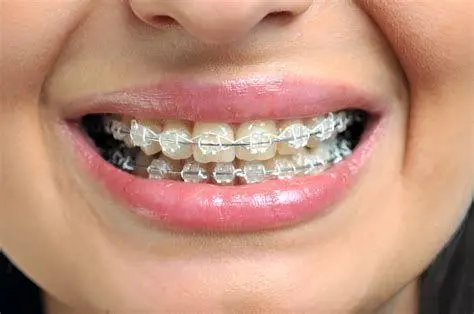

Jenis material yang dipilih merupakan penyumbang terbesar dalam struktur harga behel gigi. Teknologi bracket telah berkembang pesat dari sekadar logam tradisional hingga material keramik yang sewarna gigi atau bahkan sistem self-ligating yang diklaim lebih minim rasa sakit. Setiap inovasi teknologi ini membawa label harga yang berbeda-beda tergantung pada keunggulan estetika dan kenyamanan yang ditawarkan kepada pasien.

Behel metal tetap menjadi pilihan paling populer karena harga behel gigi tipe ini adalah yang paling terjangkau. Meskipun secara estetika terlihat mencolok, behel metal sangat tangguh untuk menangani pergeseran gigi yang ekstrem. Pasien juga dapat berkreasi dengan warna-warni karet (power-O) yang diganti setiap bulan sesuai keinginan.

2. Behel Keramik dan Sapphire

Bagi profesional atau mereka yang peduli pada penampilan, behel keramik atau sapphire menawarkan solusi estetika. Material keramik memiliki tekstur yang sedikit lebih kasar namun warnanya menyatu dengan gigi. Sementara sapphire bersifat kristal bening yang sangat estetik. Karena materialnya lebih rapuh dibandingkan logam, perawatannya membutuhkan ketelitian lebih tinggi agar bracket tidak pecah.